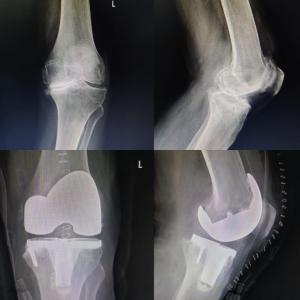

Revision Knee & Hip Replacement

Complex Joint Replacement Surgery